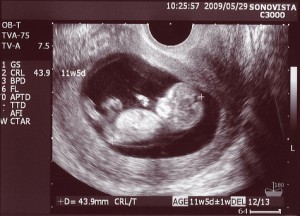

Сейчас малыш относительно хорошо защищен от внешних воздействий и инфекций, исключением является краснуха, она может вызвать аномалии развития. Будьте предельно внимательны с краснухой. Как развивается кишечник ребенка? Часть кишечника пока выпадает в пуповину, но на следующей неделе эта ситуация поправится. Кишечник начинает свою деятельность, он осуществляет сокращения, подобие перистальтики. Также на 11-12 неделе беременности начинают функционировать почки ребенка, они через плаценту выводят продукты выделения. После десятой недели беременности кровеносные сосуды и сердце работают так, как у взрослого человека. Кровь перекачивается сердцем во всех основных органах. В крови появляются первые лимфоциты - белые клетки крови, которые отвечают за иммунитет.  Печень составляет 10% общего веса ребенка. Ребенок начинает поднимать свою головку от груди, шея укрепляется и развивается. Активизируется эндокринная система, в легких выделяются бронхи и трахея, продолжают формироваться капилляры, вены и артерии. На этом сроке малыш начинает чувствовать запахи, у него появляется обоняние. Кожа на ладонях становится чувствительной, у крохи появляется хватательная реакция, он уже умеет потягиваться. Ребенок активничает, он может полностью повернуться за 2 секунды. Твердеют его кончики пальчиков, продолжается окостенение скелета, растут мышцы и сухожилия. Объем костного мозга достигает - 16мл. На 9, 10, 11 и 12 неделе беременности появляются голосовые связки, но впервые голос ребенок подаст после своего рождения. Яичники и яички уже образовались, в зависимости от того, кто у Вас родится, девочка или мальчик. Если гениталии будут правильно развернуты к экрану, на УЗИ можно будет наблюдать пол ребенка. В месте крепления плодного яйца к одной из стенок матки, окончательно формируется и развивается плацента (детское место). Плацента - это дискообразный орган, который образуется на время беременности, он связан с внешней оболочкой плодного яйца, состоит из нескольких слоев. Размеры плаценты: диаметр - 15-20см, толщина - 3-3,5см. Через плаценту к ребенку поступают питательные вещества и кислород, выводятся продукты метаболизма. Плацента не допускает смешивания крови матери и ребенка. Она служит защитным барьером для малыша. Что происходит с мамой? Ваша матка растет по мере роста малыша в ней, она имеет размер женского кулака. Движений ребенка Вы пока не ощущаете. Одежда начинает давить, значит, пора переходить на более свободный покрой. Грудь становить тяжелее, прикосновения к ней уже не такие болезненные. В этот период базальная температура снижается ниже 37°С. УЗИ 11 недель

Печень составляет 10% общего веса ребенка. Ребенок начинает поднимать свою головку от груди, шея укрепляется и развивается. Активизируется эндокринная система, в легких выделяются бронхи и трахея, продолжают формироваться капилляры, вены и артерии. На этом сроке малыш начинает чувствовать запахи, у него появляется обоняние. Кожа на ладонях становится чувствительной, у крохи появляется хватательная реакция, он уже умеет потягиваться. Ребенок активничает, он может полностью повернуться за 2 секунды. Твердеют его кончики пальчиков, продолжается окостенение скелета, растут мышцы и сухожилия. Объем костного мозга достигает - 16мл. На 9, 10, 11 и 12 неделе беременности появляются голосовые связки, но впервые голос ребенок подаст после своего рождения. Яичники и яички уже образовались, в зависимости от того, кто у Вас родится, девочка или мальчик. Если гениталии будут правильно развернуты к экрану, на УЗИ можно будет наблюдать пол ребенка. В месте крепления плодного яйца к одной из стенок матки, окончательно формируется и развивается плацента (детское место). Плацента - это дискообразный орган, который образуется на время беременности, он связан с внешней оболочкой плодного яйца, состоит из нескольких слоев. Размеры плаценты: диаметр - 15-20см, толщина - 3-3,5см. Через плаценту к ребенку поступают питательные вещества и кислород, выводятся продукты метаболизма. Плацента не допускает смешивания крови матери и ребенка. Она служит защитным барьером для малыша. Что происходит с мамой? Ваша матка растет по мере роста малыша в ней, она имеет размер женского кулака. Движений ребенка Вы пока не ощущаете. Одежда начинает давить, значит, пора переходить на более свободный покрой. Грудь становить тяжелее, прикосновения к ней уже не такие болезненные. В этот период базальная температура снижается ниже 37°С. УЗИ 11 недель  К 11-12 неделям у большинства женщин проходит токсикоз, головокружение и утомляемость, уменьшается слюнообразование. Раньше так хотелось поплакать, пообижаться, пожалеть себя, сейчас Вы более спокойные. Не перегружайте Ваши почки и печень вредной и тяжелой пищей, откажитесь от острой и жирной пищи. Не пейте много жидкости на ночь, чтобы избежать отеков. Растет объем циркулирующей крови, обмен веществ (метаболизм) увеличивается на 25%, это связано с тем, что ребенок потребляет все больше питательных веществ. У Вас может усилится потоотделение, ощущение внутреннего жара, Вам захочется постоянно пить. В этот период очень важен анализ мочи на наличие белка и лейкоцитов. Могут появится растяжки в области живота, груди, на бедрах и ягодицах. После беременности они, как правило будут светлее, но полностью не исчезнут. Рекомендуется для профилактики применять средства от растяжек и зуда кожи живота.

К 11-12 неделям у большинства женщин проходит токсикоз, головокружение и утомляемость, уменьшается слюнообразование. Раньше так хотелось поплакать, пообижаться, пожалеть себя, сейчас Вы более спокойные. Не перегружайте Ваши почки и печень вредной и тяжелой пищей, откажитесь от острой и жирной пищи. Не пейте много жидкости на ночь, чтобы избежать отеков. Растет объем циркулирующей крови, обмен веществ (метаболизм) увеличивается на 25%, это связано с тем, что ребенок потребляет все больше питательных веществ. У Вас может усилится потоотделение, ощущение внутреннего жара, Вам захочется постоянно пить. В этот период очень важен анализ мочи на наличие белка и лейкоцитов. Могут появится растяжки в области живота, груди, на бедрах и ягодицах. После беременности они, как правило будут светлее, но полностью не исчезнут. Рекомендуется для профилактики применять средства от растяжек и зуда кожи живота.  Возможно Вы уже впервые обследовались на УЗИ, впервые увидели малыша, услышали, как бьется его сердце. Поспрашивайте своего врача о курсах для беременных, поищите информацию сами в интернете. По поводу посещения стоматолога во время беременности: если необходимо лечение зубов, по возможности отложите визит к зубному врачу до наступления двенадцати недель беременности. Избегайте общей анестезии. Если же у Вас инфекция и очень сильно болит зуб, обязательно посетите зубного врача. Во время беременности десны становятся более чувствительными и могут кровоточить, не забывайте регулярно чистить и полоскать рот. Не злоупотребляйте алкоголем, никотином и химическими веществами. Как это прекрасно чувствовать, что у Вас происходят волшебные созидательные процессы. Мы желаем Вам хорошего здоровья, понимания, бережного отношения, помощи и поддержки от супруга и близких!

Возможно Вы уже впервые обследовались на УЗИ, впервые увидели малыша, услышали, как бьется его сердце. Поспрашивайте своего врача о курсах для беременных, поищите информацию сами в интернете. По поводу посещения стоматолога во время беременности: если необходимо лечение зубов, по возможности отложите визит к зубному врачу до наступления двенадцати недель беременности. Избегайте общей анестезии. Если же у Вас инфекция и очень сильно болит зуб, обязательно посетите зубного врача. Во время беременности десны становятся более чувствительными и могут кровоточить, не забывайте регулярно чистить и полоскать рот. Не злоупотребляйте алкоголем, никотином и химическими веществами. Как это прекрасно чувствовать, что у Вас происходят волшебные созидательные процессы. Мы желаем Вам хорошего здоровья, понимания, бережного отношения, помощи и поддержки от супруга и близких!